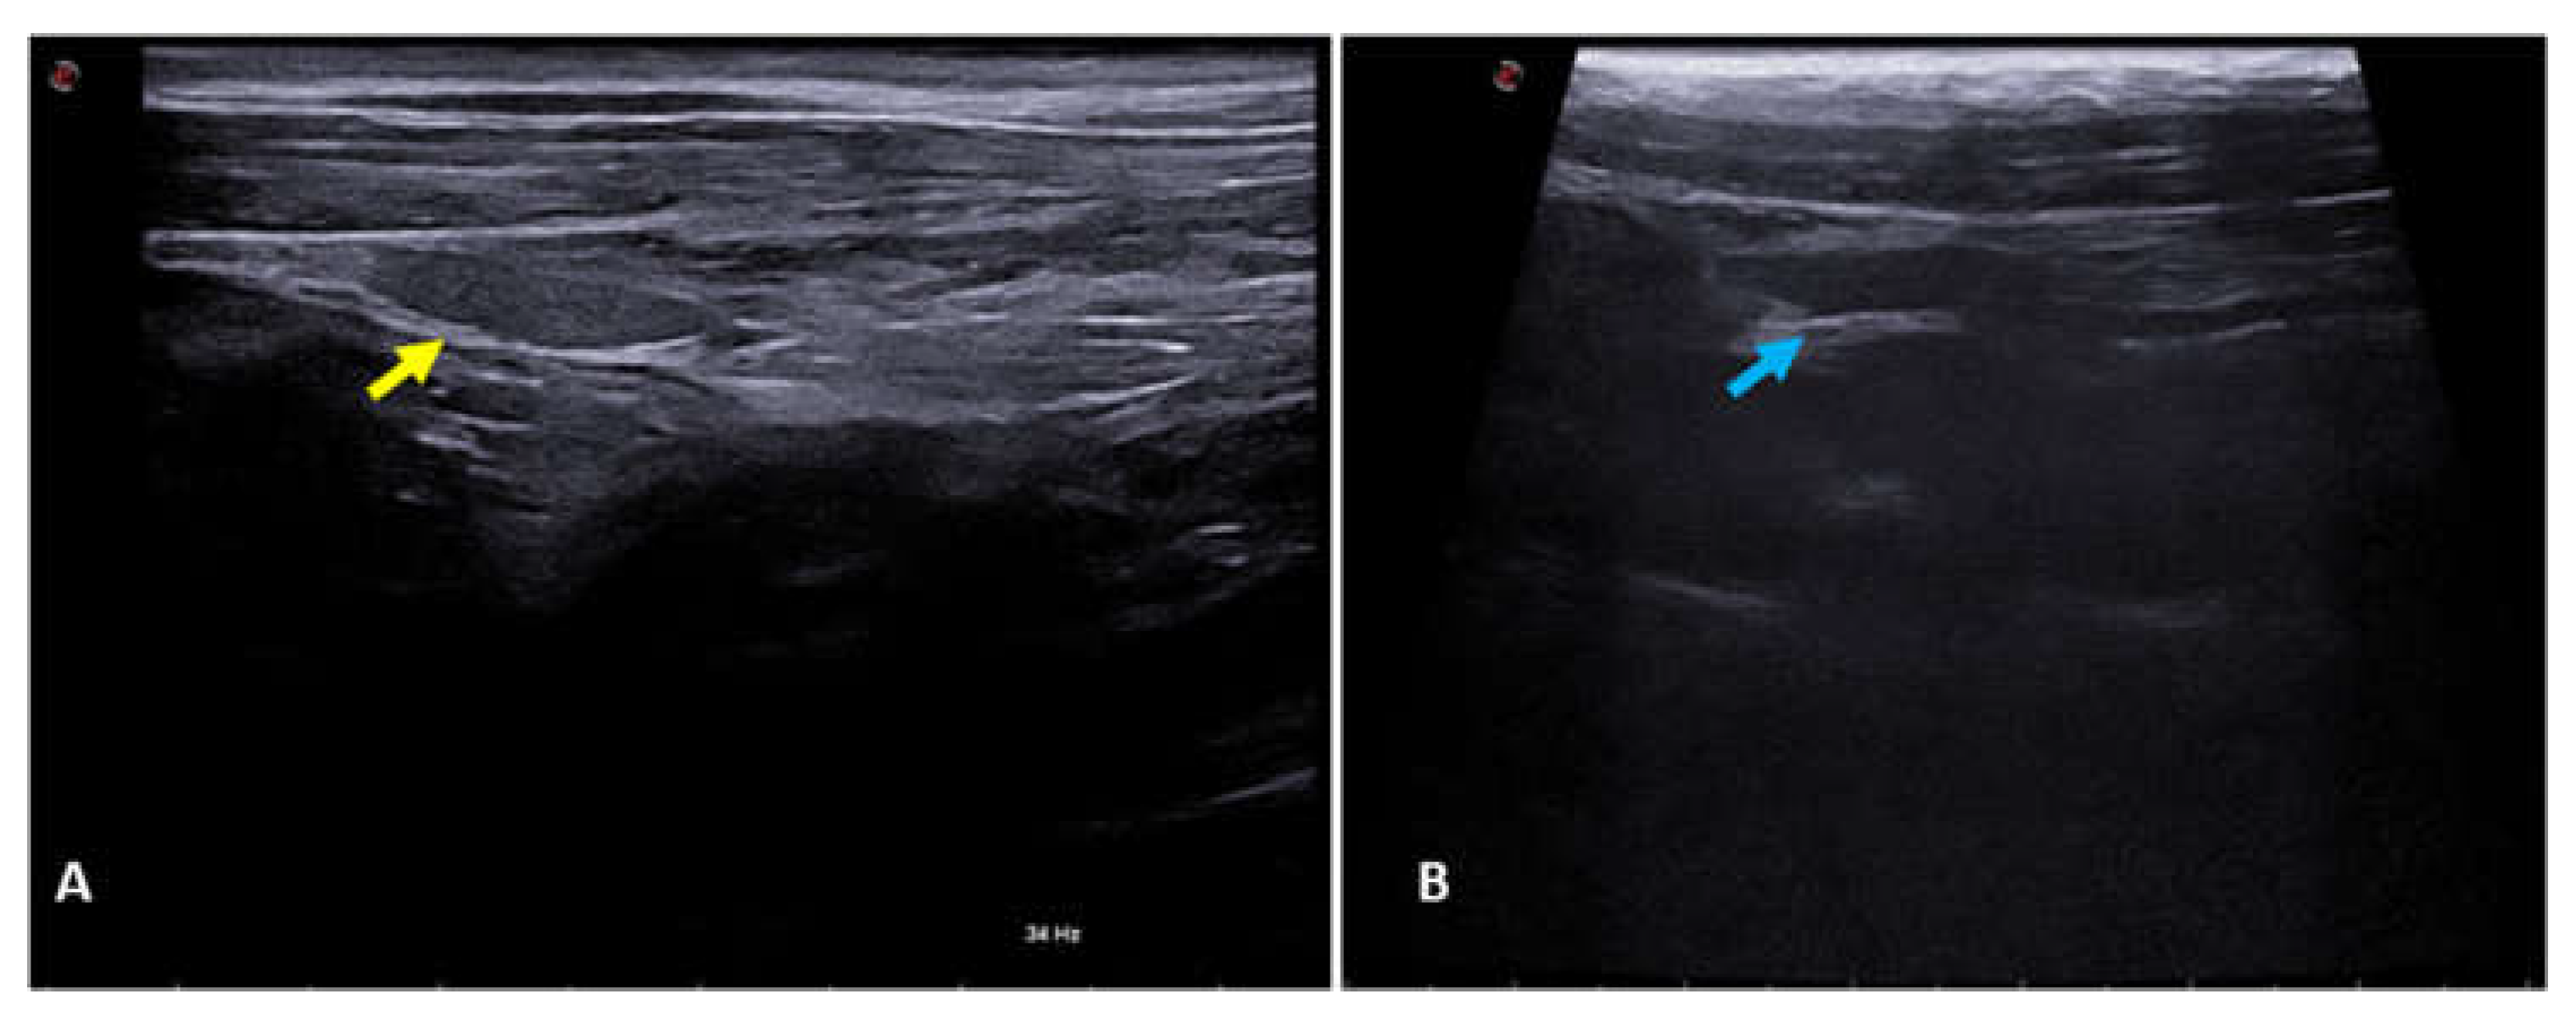

2.4. B-Mode Thyroid Ultrasonography

B-mode ultrasound study of the thyroid was carried out using MyLabTM X8 Platform equipment (Esaote, Italy), with a 4-15 MHz multi-frequency and linear transducer. All the gain, frequency, focus, TCG and depth settings were adapted according to the physical characteristics of each dog participating in the study. The thyroid gland lobes were located in their usual topography, between the sternocephalic and sternothyroid muscles, ventral to the trachea and caudal to the larynx. Both were assessed in a longitudinal section for their dimensions (length and width), echogenicity in relation to the adjacent muscles (hypoechogenic, isoechogenic or hyperechogenic) and surface regularity. The aforementioned characteristics were also assessed in cross-section, except for dimensions (Figure 1). Figure 2 shows the two thyroid lobes on B-mode ultrasound in a longitudinal section of dogs of different ages. Figure 2A shows the right thyroid lobe of a 3-year-old female dog, with homogeneous and hyperechogenic parenchyma, regular contours and an ellipsoid shape. Figure 2B shows the right thyroid lobe of a 7-year-old female dog, with homogeneous and hyperechogenic parenchyma, regular contours and an ellipsoid shape.

Figure 1. - B-mode ultrasound image of the right (yellow arrow) and left (blue arrow) thyroid lobes of a 9-year-old female dog.

Figure 2. - B-mode ultrasound image of the right thyroid lobes of female dogs of different ages. (A) Right thyroid lobe (yellow arrow) of a 3-year-old female dog. (B) Right thyroid lobe (blue arrow) of a 7-year-old female dog.